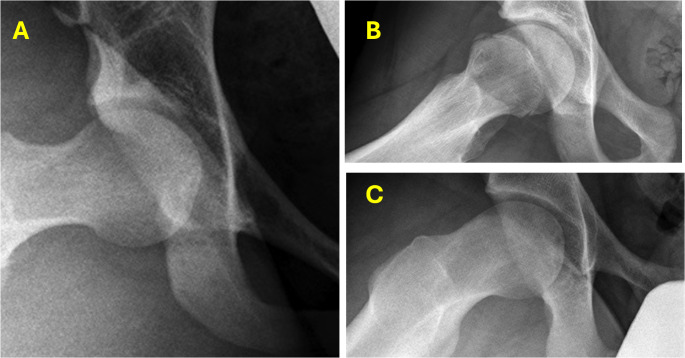

Abstract Image